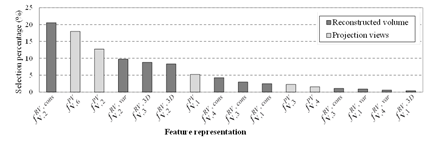

그림 2. 제안 boosting 기반 분류 방법에서 각 특징 정보가 선택된 비율. 단면영상과 투영영상에서 추출된 특징 정보가 모두 활용되기 때문에 두 영상 특성이 상보적임을 보임.

In digital breast tomosynthesis (DBT), image characteristics of projection views and reconstructed volume are different and both have the advantage of detecting breast masses, e.g. reconstructed volume mitigates a tissue overlap, while projection views have less reconstruction blur artifacts. In this paper, an improved mass detection is proposed by using combined feature representations from projection views and reconstructed volume in the DBT. To take advantage of complementary effects on different image characteristics of both data, combined feature representations are extracted from both projection views and reconstructed volume concurrently. An indirect region-of-interest segmentation in projection views, which projects volume-of-interest in reconstructed volume into the corresponding projection views, is proposed to extract combined feature representations. In addition, a boosting based classification with feature selection has been employed for selecting effective feature representations among a large number of combined feature representations, and for reducing false positives. Experiments have been conducted on a clinical data set that contains malignant masses. Experimental results demonstrate that the proposed mass detection can achieve high sensitivity with a small number of false positives. In addition, the experimental results demonstrate that the selected feature representations for classifying masses complementarily come from both projection views and reconstructed volume.Author information

- 최근 digital breast tomosynthesis (DBT)가 새로운 유방 영상 촬영술로 주목을 받고 있습니다. DBT의 2차원 투영영상(projection views)과 3차원 단면영상(reconstructed volume)은 상보적 영상 특성을 가지고 있어, 병변(mass) 자동 검출에 두 영상 정보를 모두 분석하는 것이 효과적 입니다. 이를 위해 본 논문은 두 영상에서 병변의 융합 특징 정보를 추출하고, boosting 및 다중 분류기 기반 병변 특징 선택/분류 방법을 제안하였습니다. 실험을 통해 두 영상 정보를 모두 분석 시 병변 분류 성능이 향상됨을 보였고 (그림 1), 분류에 중요한 병변 정보를 포함하여 자주 선택된 특징 정보들이 두 영상에 모두 분포하여 상보적임을 보였습니다 (그림 2). 또한 기존 정보 융합 방법 대비 우수한 분류 성능을 보여 (그림 3) DBT 투영영상과 단면영상 특징 융합 분석, 위양성 감소 (그림 4)에 효과적임을 보였습니다. 본 연구는 다중 영상 융합 분석, DBT 영상 특징 분석에 관심 있는 연구자들에게 도움이 될 좋은 정보라 생각합니다.